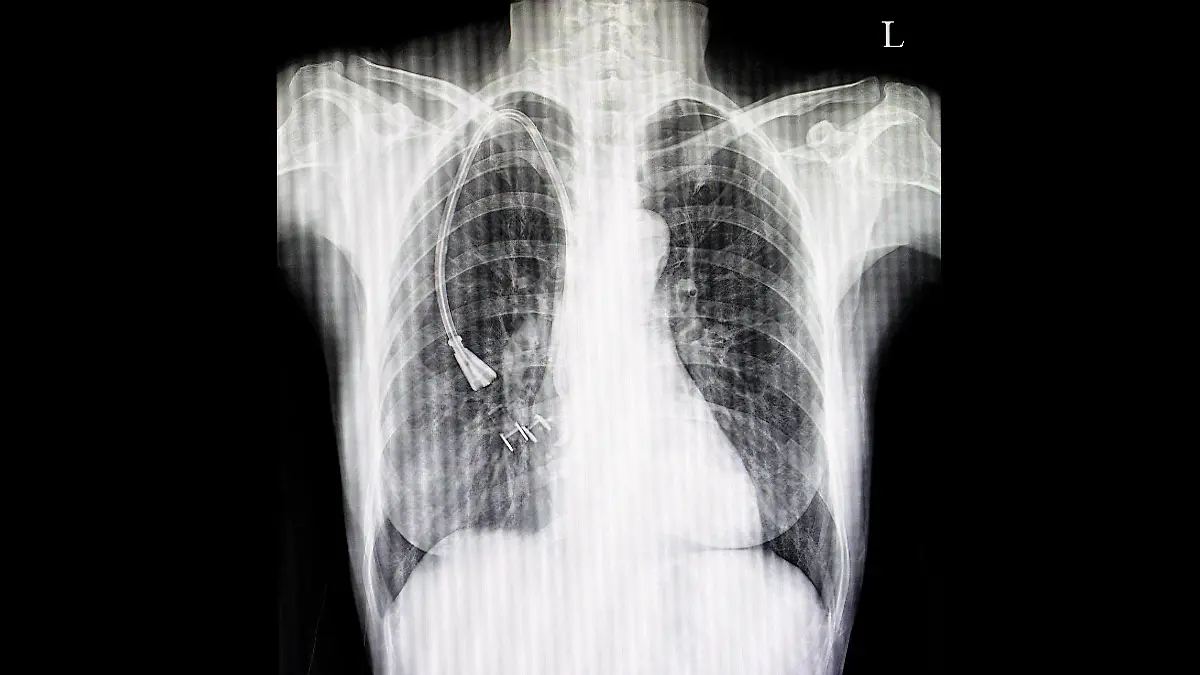

Eine Thoraxdrainage besteht grundsätzlich aus einem Schlauch, der in die flüssigkeits- oder luftgefüllte Höhle eingeführt wird, und angeschlossenen Kammern, die zum Absaugen und Auffangen der Substanzen bereitstehen. Das ursprüngliche Einkammersystem bestand aus einer Flasche, in die die Flüssigkeit mittels des Drainageschlauches abgeleitet wurde. Der Sog wurde durch den Unterdruck erzeugt, der durch den in Flüssigkeit eingetauchten Schlauch und die Schwerkraft entstand. Beim Zweikammersystem kam eine zweite Flasche hinzu, sodass die Abgabe der Flüssigkeit und die Sogentwicklung in getrennten Räumen stattfinden konnten. Das heute am häufigsten eingesetzte System besteht aus drei Kammern, bei dem in der dritten Flasche zusätzlich die Stärke der Sogentwicklung kontrolliert wird. Die Pumpleistung wird durch ein Vakuum erzeugt, dass angeschlossene Vakuumanlagen oder Druckluftwandler erzeugen. Die Funktion der Pumpen kann auch umgekehrt werden, um zum Beispiel Antibiotikalösungen ins Innere von Höhlen zu transportieren, die mit Bakterien befallen sind. Es gibt auch aufwendige digitale Systeme, in denen alle Funktionen automatisch gesteuert und kontrolliert werden. Sie sind zwar teuer und aufwendig, bieten aber den Vorteil, dass Alarmsysteme die Sicherheit der Patienten gewährleisten und gleichzeitig Vitalfunktionen gemessen und beobachtet werden können.

Eine Pleuradrainage kann an verschiedenen Stellen angelegt werden, es gibt aber zwei bevorzugte Zugangswege. Die Monaldi-Lokalisation befindet sich mittig unterhalb des Schlüsselbeins zwischen der zweiten und dritten Rippe, die Bülau-Lokalisation unterhalb der Achselhöhle in einem Zwischenraum im Bereich der vierten bis sechsten Rippe. Für den Zugang werden die Haut und das Brustfell punktförmig eröffnet und anschließend der Schlauch mit einer metallenen Führungsschiene in die Pleurahöhle eingeführt. Nach Entfernung des Metallstabes wird der verbleibende Kunststoffschlauch an der Haut befestigt, um ein Verrutschen zu verhindern, und an das Absaugsystem angeschlossen.